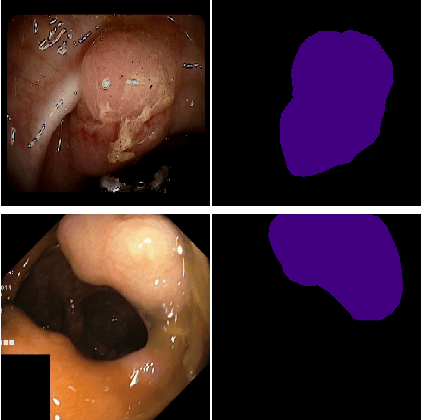

Abstract:Colorectal cancer (CRC) is the first cause of death in many countries. CRC originates from a small clump of cells on the lining of the colon called polyps, which over time might grow and become malignant. Early detection and removal of polyps are therefore necessary for the prevention of colon cancer. In this paper, we introduce an ensemble of medical polyp segmentation algorithms. Based on an observation that different segmentation algorithms will perform well on different subsets of examples because of the nature and size of training sets they have been exposed to and because of method-intrinsic factors, we propose to measure the confidence in the prediction of each algorithm and then use an associate threshold to determine whether the confidence is acceptable or not. An algorithm is selected for the ensemble if the confidence is below its associate threshold. The optimal threshold for each segmentation algorithm is found by using Comprehensive Learning Particle Swarm Optimization (CLPSO), a swarm intelligence algorithm. The Dice coefficient, a popular performance metric for image segmentation, is used as the fitness criteria. Experimental results on two polyp segmentation datasets MICCAI2015 and Kvasir-SEG confirm that our ensemble achieves better results compared to some well-known segmentation algorithms.